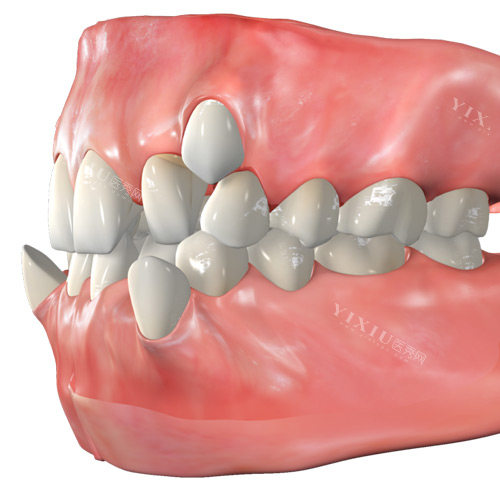

二、牙齿矫正价格明细 (牙齿美容核心项目)

无论是成人还是青少年,快乐蜗牛口腔都能提供个性化的牙齿矫正方案,让笑容更自信。

传统金属托槽矫正(青少年普适型):5200元起

金属自锁托槽矫正(较高的效率舒适):8500元起

陶瓷半隐形托槽矫正:11000元起

陶瓷自锁半隐形托槽矫正:14500元起

国产正雅Smartee隐形矫正(经典版):16000元起

国产时代天使Angelalign隐形矫正(标准版/COMFOS):18800元起

国产时代天使Angelalign隐形矫正(冠军版):30000元起

美国进口隐适美Invisalign隐形矫正:35000元起

儿童早期矫正ETA/罗慕/法兰克:6000元起/阶段